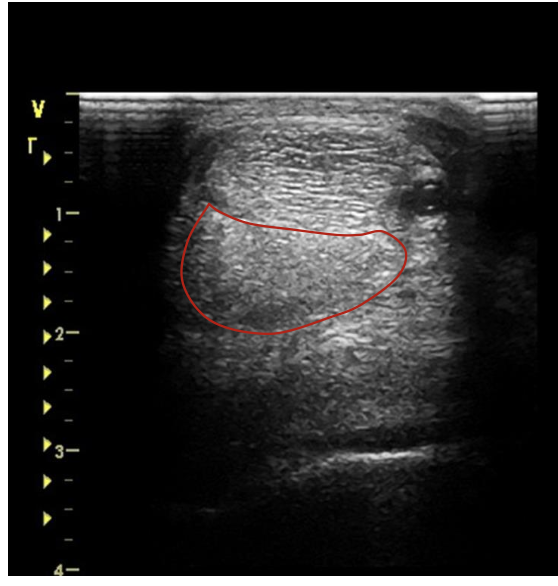

what is the red circling?

DDFT just below the carpal joint

DDFT mid MC 3

DDFT at proximal fetlock joint